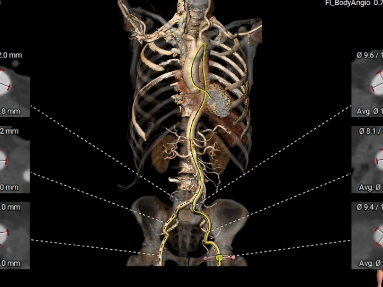

术前CT评估:三叶瓣,无钙化,瓣叶情况好,下肢动脉情况好。

主动脉瓣环直径25.8

瓣环上2 27.3

瓣环上4 27.3

LVOT

SOV

STJ

左冠高度10.8

右冠高度12.6

主动脉瓣环角度38°

舒张期瓣环直径25.3

舒张期瓣环2直径29.5

外周血管入路

手术策略

该例患者为75岁老人,患者左心室增大一般情况较差,外科开胸手术风险极高,术前CT提示主动脉瓣环周长折算直径约25.8mm,计划采用28mm的杰成主动脉瓣膜,术中需确保定位件置于窦底,精准释放,因患者心功能储备差,使用杰成瓣膜可尽可能简化流程,缩短手术时间,术中需密切监测患者的生命体征及血流动力学。